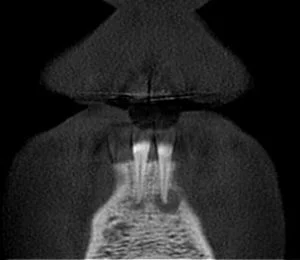

A CBCT was taken after a negative cold test indicated a necrotic tooth. When the CBCT was taken, we could clearly see that the abscess had completely perforated the labial bone at the apex of #24 and was close to doing so on #25.

As we investigated more deeply, we identified another critical piece of information that would affect our treatment plan: a second canal on #24.